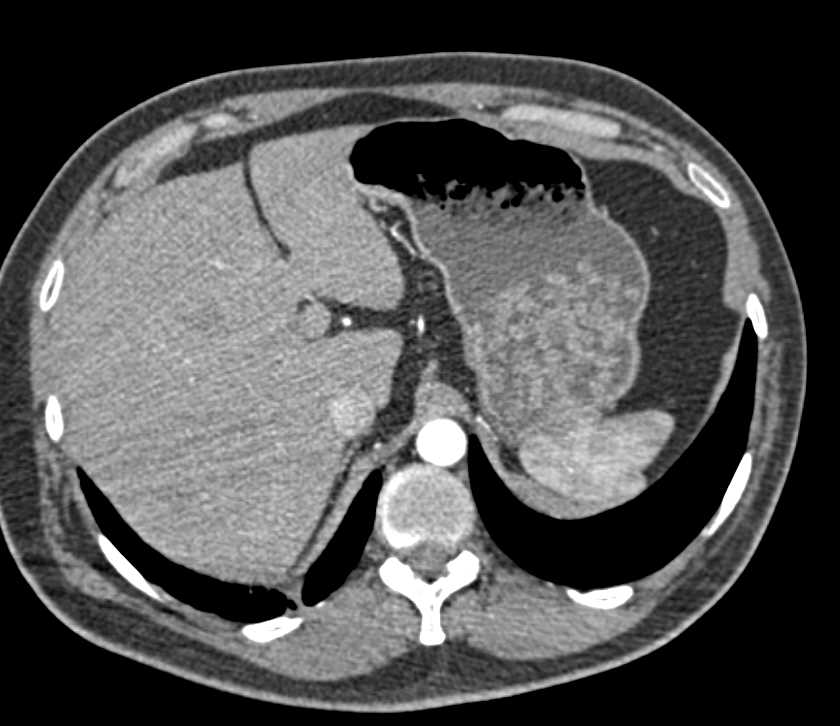

Old Calcified Adrenal Adenoma